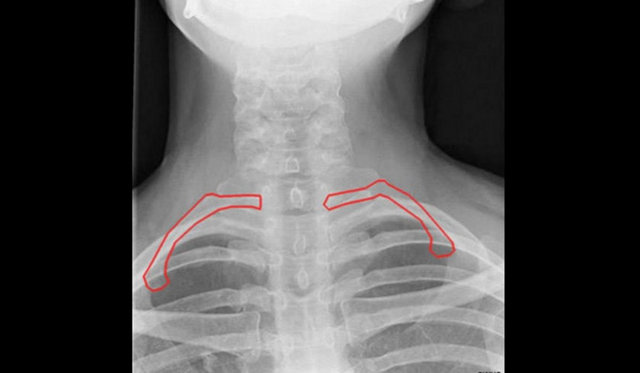

HABERTURK.COM / SAĞLIK SERVİSİ Cadılar Bayramı için 10 Sterline aldığı ilginç lensi takan 24 yaşındaki Sarah Richards, lensin gözbebeklerine yapışması nedeniyle neredeyse kör oluyordu...

Lensi taktıktan birkaç saat sonra şiddetli bir acıyla karşı karşıya kaldığını söyleyen Richards, gözünün enfeksiyon kapması nedeniyle bir hafta çalışamadığını söylüyor.

Daha önce hiç lens takmadığını söyleyen genç kadın, "Lensi taktığımda onun plastik ve konforsuz olduğunu düşündüm" diyor.

Arkadaşının partisine giden Richards, lensini çıkarmadan uyudu. Sabah kalktığında yolunda gitmeyen bir şeyler olduğunu fark eden genç kadın, "Acılar içinde uyandım.

Gözlerimi açmaya çalıştım, nihayet gözümü açabildiğimde küçücük bir ışık gördüm" diyor.

Lensleri gözünden attığında, onların makyaj ve yapışkan ile kaplı olduğunu gördüğünü söylüyor.

Korkular içerisinde doktora giden genç kadının gözlerine damla damlatılarak, göz banyosu yaptırıldı.

İyileşen genç kadın, cadılar bayramı nedeniyle milyonlarca insanın birbirinden ilginç lensler alacağını ama bunu kesinlikle önermediğini söylüyor.

Dr. David Allamby ise, bu tip lenslerle uyunduğu takdirde gözde enfeksiyon riskini artacağına dikkat çekerek, bu lenslerin göze kalıcı hasarlar verebileceğini söylüyor ve insanları dikkatli olmaları konusunda uyarıyor.